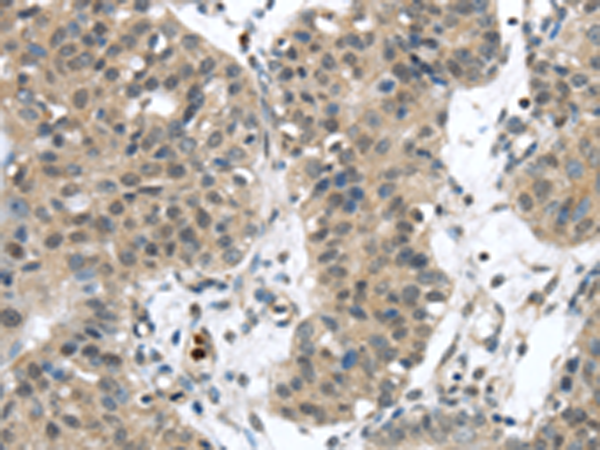

分类: 科研抗体货号: P05233别名: RNF35应用: IHC反应种属: Human